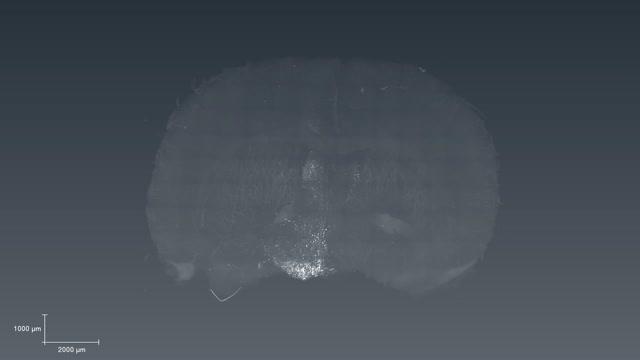

Brain Networks Involved in Drive to Stop or Keep Feeding

video: This 3-D video of activity in certain areas of a mouse brain is one of several created with the results of research on the role of POMC and AgRP neurons in feeding behavior. The videos can be seen here: http://michmed.org/EXGOq view more

Credit: Akil laboratory, University of Michigan

The team also used a new method called CLARITY to visualize in 3-D the pathways that start from POMC and AgRP neurons. These pathways of neurons, once activated, can trigger either a sense of feeling full - called satiety -- or the drive to eat. They stitched together images of activated neurons in a computer, to create 3-D videos that show the neurons' reach. The vides can be seen here: http://michmed.org/EXGOq